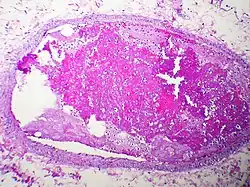

Embolism by other materials is rare. Septic embolism happens when a purulent tissue (pus-containing tissue) is dislodged from its original focus. Tissue embolism is analogous to macro-scale cancer metastasis, which happens when cancer tissue infiltrates blood vessels, and small fragments of tumor are released into the blood stream. Foreign-body embolism happens when exogenous—and only exogenous—materials such as talc enter the blood stream and cause occlusion or obstruction of blood circulation. Bullet embolism occurs in approximately 0.3% cases of gunshot wounds.[8] Amniotic-fluid embolism is a rare complication of childbirth.